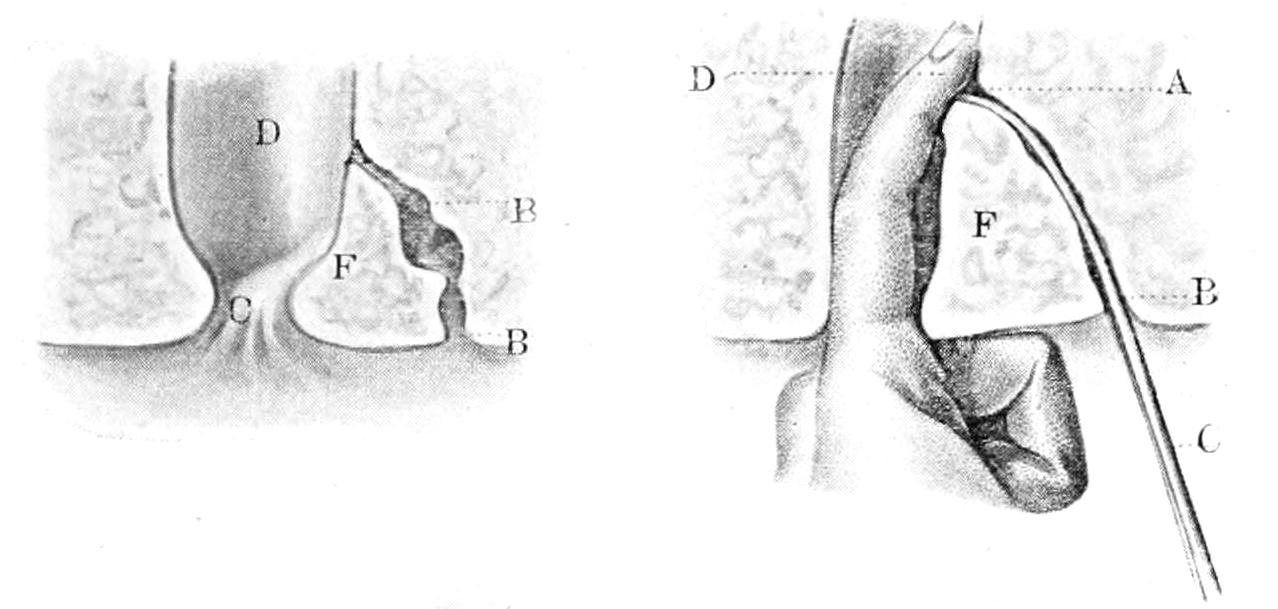

Fig. 178

Fig. 179

Surgical anatomy and ligation of the posterior tibial artery. (Bernard and Huette).

[360]